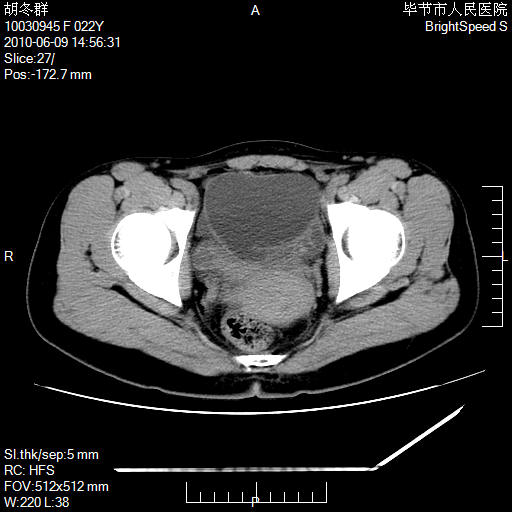

患者23岁,发现腹部包块3月。

盆腔内囊性占位;穿刺或者直接手术拿掉即可,不必紧张。

左侧卵巢囊腺瘤或囊腺癌

盆腔内囊性占位性病变;考虑左侧卵巢囊腺瘤。

有分隔、壁薄,支持考虑左侧卵巢囊腺瘤。

左侧卵巢浆液性囊腺瘤。

支持考虑左侧卵巢囊腺瘤;宫腔积液。

有分隔、壁薄,支持考虑左侧卵巢囊腺瘤。排尿后,膀胱缩小,由于重力作用,肿块下移就到了膀胱位置,很好理解。